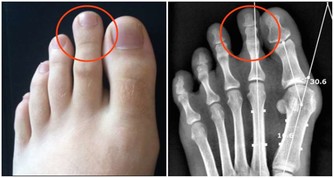

5、手指

不少存在嚴重肺部疾病的人,會出現杵狀指的情況,較為常見的就是手指頭增生粗大。

因此,想判斷肺部功能好不好,也可多觀察手指。若是手指粗細均勻,沒有指頭粗大現象,就說明肺部功能良好;而若是已經出現杵狀指,就可能是肺部病變了,建議及時就醫。